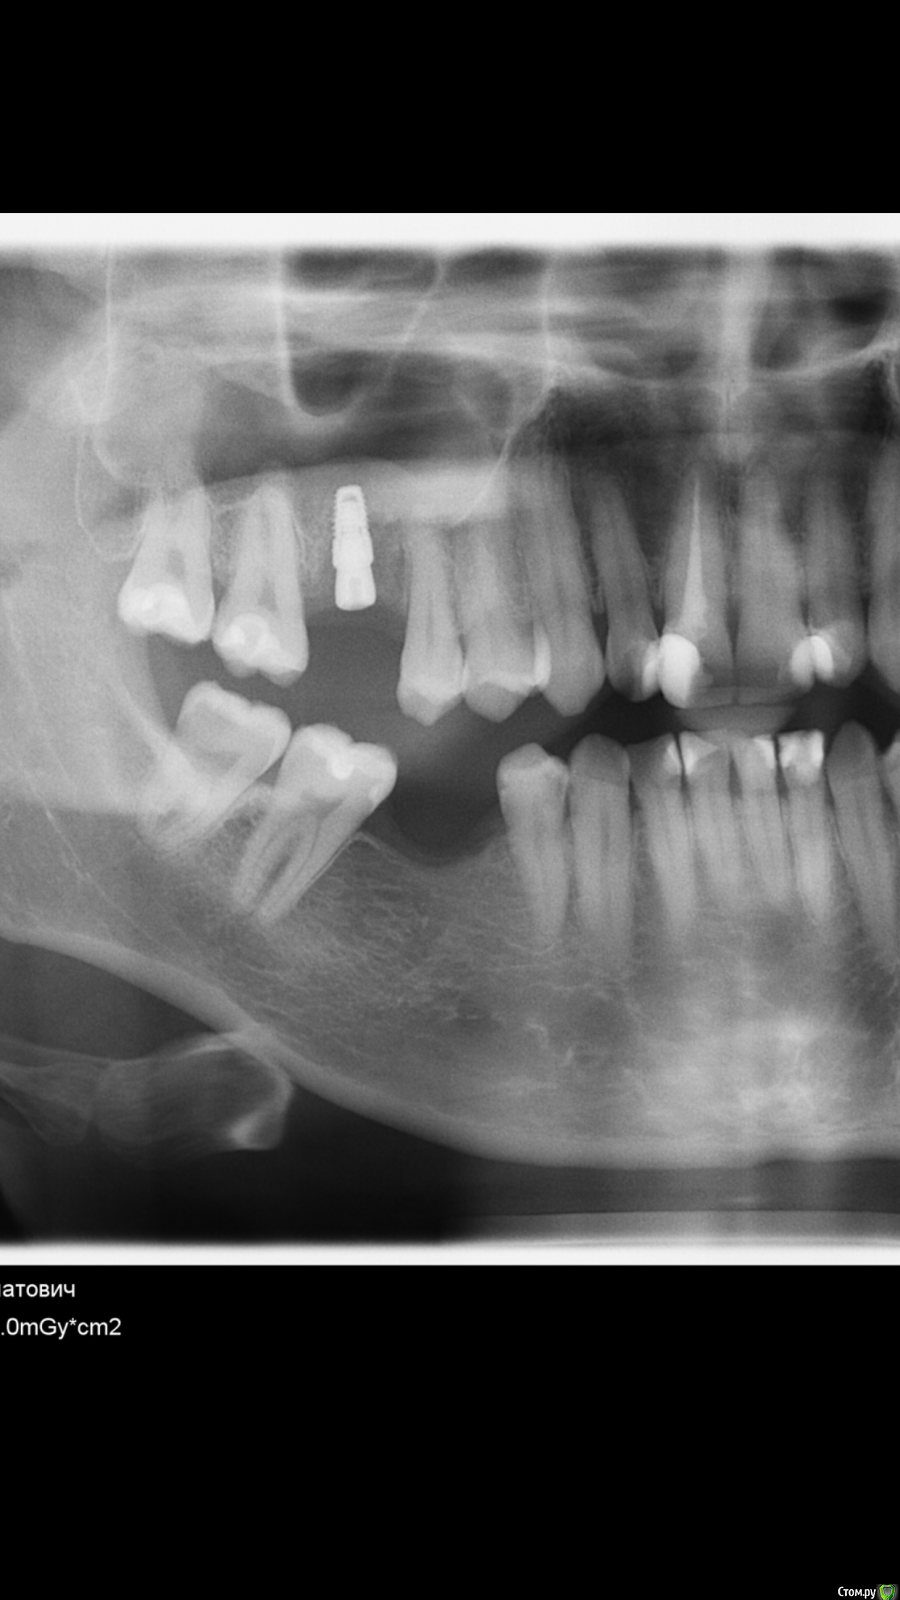

DrDimedrol Опубликовано 5 июня, 2020 Поделиться Опубликовано 5 июня, 2020 (изменено) На самом первом кейсе похоже на перегрев, вокруг апекса импланта на первых снимках есть характерная картинка (2-3-4-ий снимок). Ирригация слабая или агрессивная сверление. Изменено 5 июня, 2020 пользователем DrDimedrol Ссылка на комментарий

ilnurik Опубликовано 5 июня, 2020 Автор Поделиться Опубликовано 5 июня, 2020 На самом первом кейсе похоже на перегрев, вокруг апекса импланта на первых снимках есть характерная картинка (2-3-4-ий снимок). Ирригация слабая или агрессивная сверление.Одномоментная имплантация на первом кейсе. может в спортивный зал начали ходить?Если бы, не могу себя заставить Ссылка на комментарий